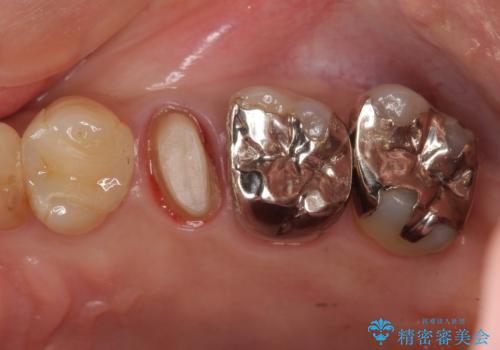

- 左上5番の根の治療途中で転院希望で来院。

割れているために抜かないといけないと説明されたとのことでした。

特に割れている所見はなかったため、根の治療から被せ物まで治療を行いました。

奥の銀歯のやりかえも希望されたため、セラミッククラウン、インレーにする治療をしています。

左上6番のアンレーは、歯の破折を防ぐためにクラウンとしました。